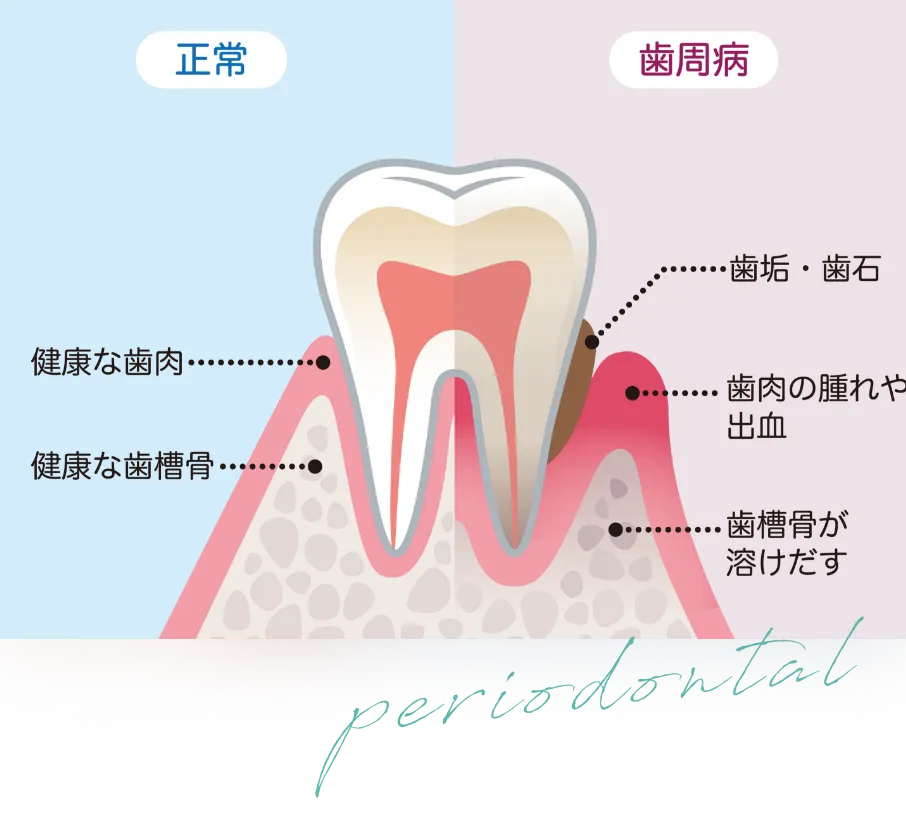

歯周病治療とは?

歯周病は日本人の半数がかかってる病気です。

歯周病(歯槽膿漏)は、歯茎に炎症を起こし、歯を支えている顎の骨を溶かしてしまう病気です。

痛みや目立った症状も少ないため、治療をしないまま過ごす方がとても多いです。

そのままにしてしまうと、徐々に症状は悪化し、 最終的には歯が抜け落ちてしまうので、正しい知識や早めの対策・ケアをしていくことが大切です。

歯周病の進行度とその症状

健康な歯

濃いピンク色の引き締まった

歯肉で、歯磨きでも出血しない

進行中度

腫れと、歯と歯茎との隙間や

歯磨きの時の出血が見られる

進行重度

歯の隙間が更に広がり、出血や膿、最悪の場合歯が抜け落ちる

気づかない内に進行するので放っておくと歯を失ってしまう恐れも